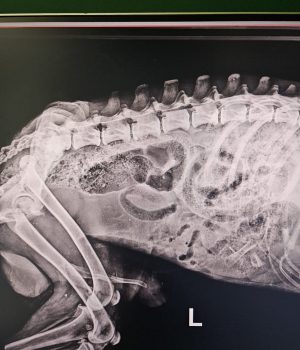

Seine Verletzungen waren schwer: mehrere Brüche der hinteren Gliedmaßen, schlechte Blutwerte und massive Verletzungen im Gesichtsbereich.

Inzwischen hat er zwei schwere Operationen an den hinteren Beinen sowie eine aufwendige Gesichtsrekonstruktion erstaunlich gut überstanden.

Der Kiefer selbst war glücklicherweise intakt. 🙏